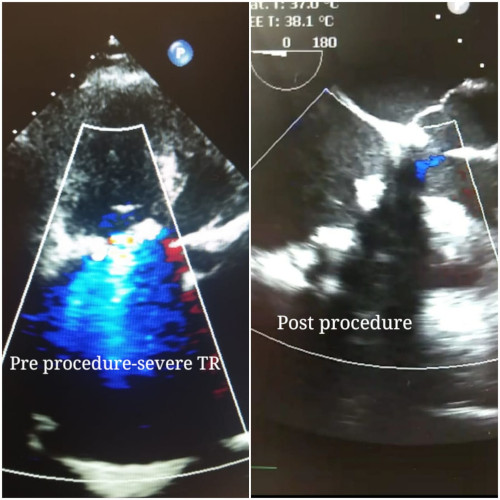

A physical examination, Echocardiogram and CT Aortogram was performed to evaluate the size of the heart and determine whether there was any extra fluid in the heart or lungs, as well as other procedures to check the heart and assess any potential damage. The patient successfully underwent Tricuspid valve in valve implantation on 11 October 2021.

�Through a vein puncture in the groin, we accessed her heart and implanted a MYVAL 27.5mm tricuspid valve within the previous bioprosthetic valve. This procedure typically takes about an hours� time to complete. She was extubated the same day and had an uneventful recovery,� said Dr. Venkatesh.